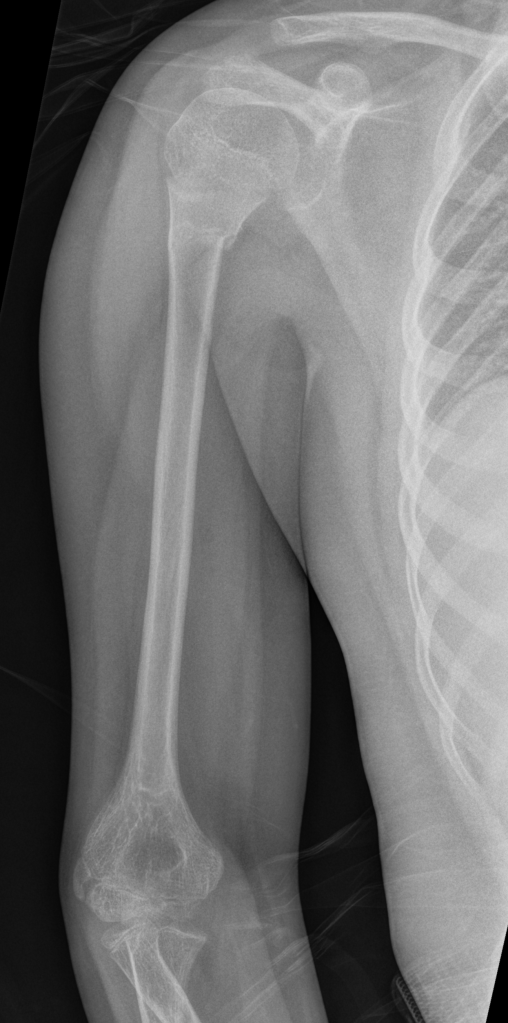

Frontal and lateral views of minimally angulated incomplete (greenstick) fracture through the proximal metaphysis. No extension to the physis. Normal glenohumeral alignment.